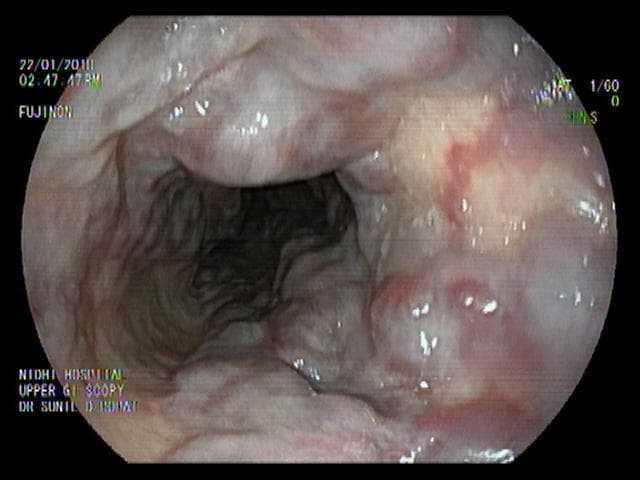

Upper endoscopyallows the doctor to examine the lining of the upper part of the gastrointestinal (GI) tract, which includes the esophagus, stomach and duodenum (first portion of the small intestine). In upper endoscopy, the physician uses a thin, flexible tube called an endoscope. The endoscope has a lens and light source, which projects images on a video monitor. This procedure is also referred to as UGI endoscopy, or esophagogastroduodenoscopy (EGD). Upper endoscopy is often done under sedation to assure maximal patient comfort.

Upper endoscopy helps the doctor evaluate symptoms of persistent upper abdominal pain, nausea, vomiting, or difficulty swallowing. It is the best test for finding the cause of bleeding from the upper GI tract and is also more accurate than X-rays for detecting inflammation, ulcers, and tumors of the esophagus, stomach, and duodenum.

A physician may also use upper endoscopy to obtain small tissue samples (biopsies). A biopsy helps distinguish between benign and malignant (cancerous) tissues. Biopsies are taken for many reasons, and a doctor might order a biopsy even if cancer is not suspected. For example, a biopsy can be taken to test for Helicobacter pylori, bacteria that can cause ulcers.

Upper endoscopy can also be used to perform a cytology (cell) test, in which a small brush is passed through the channel of the endoscope to collect cells for analysis. Other instruments can be passed through the endoscope to directly treat many abnormalities with little or no discomfort. For example, the doctor may stretch a narrow area (a stricture), detect Barrett’s esophagus (a possibly precancerous alteration in the esophageal lining), detect and biopsy gastrointestinal cancers, remove polyps (usually benign growths) treat bleeding (with standard cautery or the newer argon plasma coagulation method), and detect and treat symptoms of gastroesophageal reflux disease (GERD).